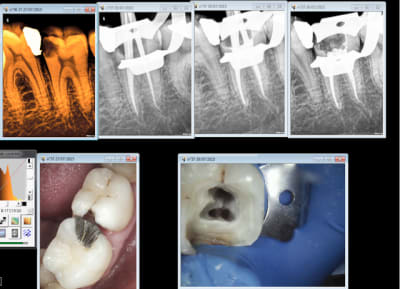

30/07/2015 à 14h53

Ca c'est pas mal non plus en 45 mn, on se demande pourquoi thermo compacer au mac spadden et j'ai perdu un morceau de crochet au passage ! -)))))

Capture d e cran 2015 07 30 12.41 - Eugenol

Capture d e cran 2015 07 30 12.49 - Eugenol

Capture d e cran 2015 07 30 12.52 - Eugenol

Capture d e cran 2015 07 30 12.48 - Eugenol